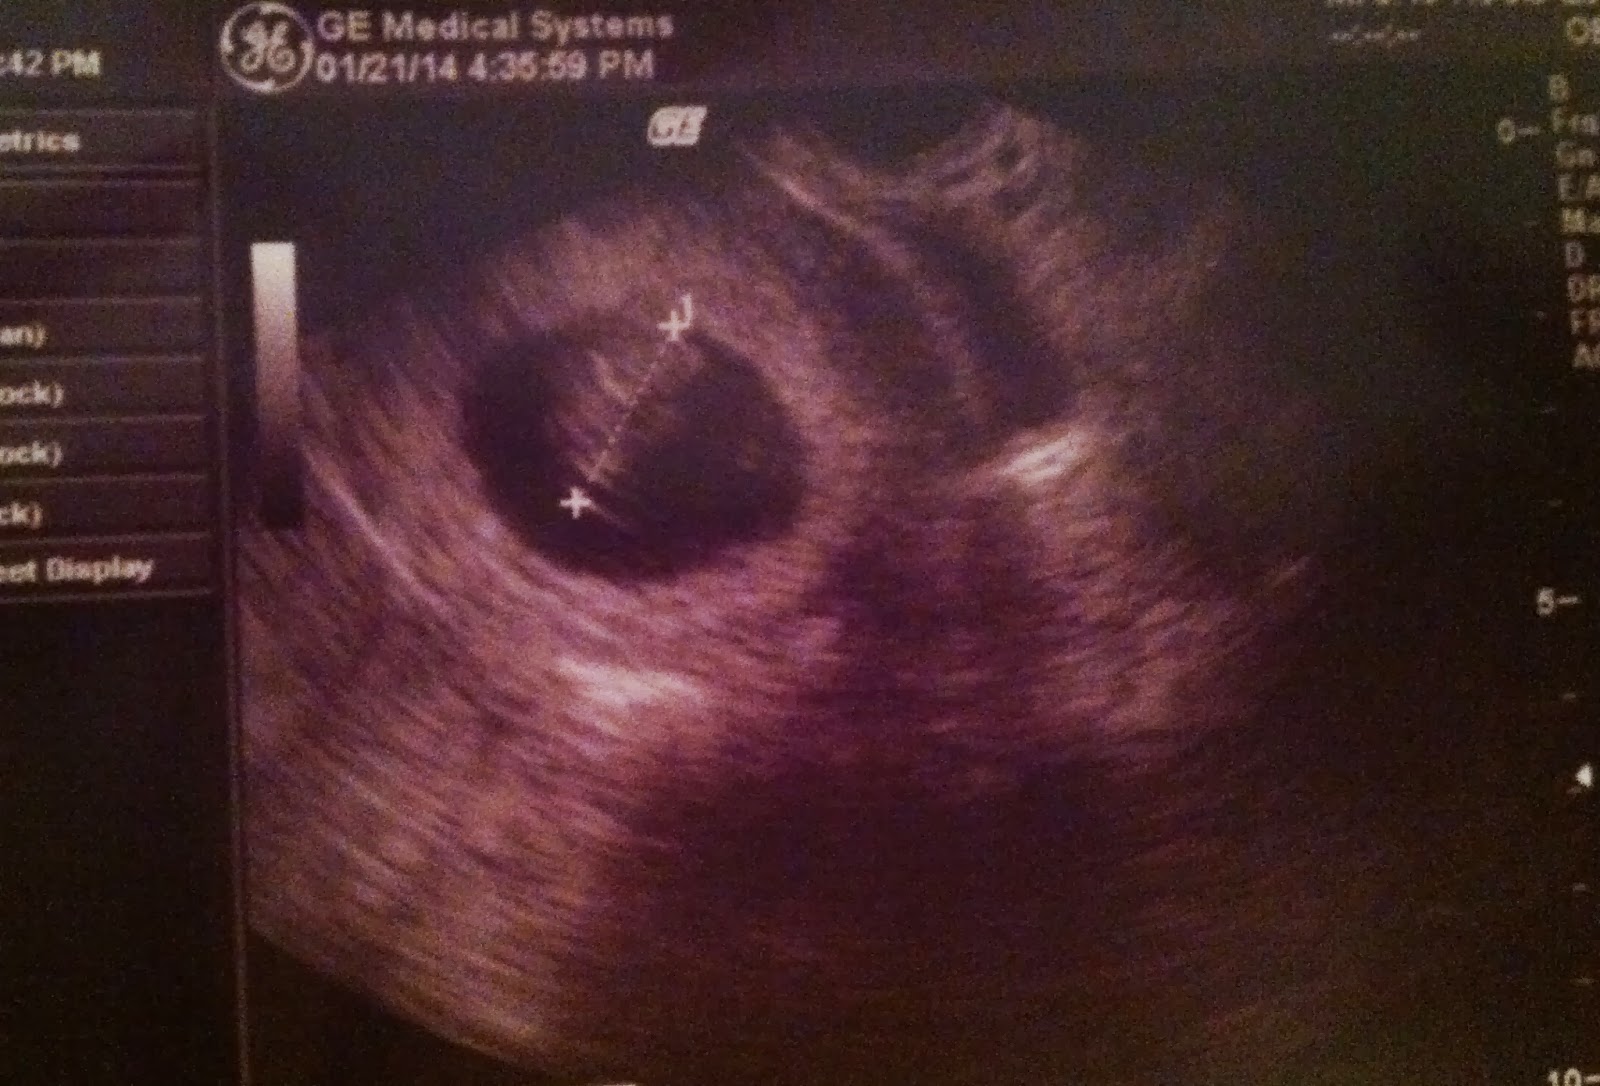

First trimester - 9 weeks and 4 days along

Baby is about the size of a grape.